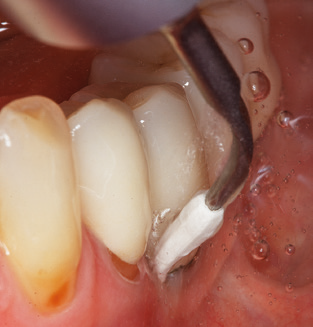

Fig. 4: Flexible probes with millimetre markings are recommended for the probing of dental implants (e.g. Colorvue Kit PCV11KIT6, Hu­Friedy). – Fig. 5a and b: A straight working tip (1P, W&H Dentalwerk Bürmoos GmbH) is a suitable instrument for use on all natural teeth. – Fig. 6: Curved working tips (3Pr/3Pl, W&H Dentalwerk Bürmoos GmbH) lend themselves to the processing of difficult-to-reach areas of the tooth and root surfaces (e.g. furcations). – Fig. 7: The tapered, hexagonal implant cleaning tip (1I, W&H Dentalwerk Bürmoos GmbH) permits atraumatic and efficient cleaning of the crown and abutment surfaces. – Fig. 8: Titanium and carbon curettes are suitable instruments for the manual cleaning of the implant surfaces.

Good illumination of the working field facilitates the process considerably. The system used by the authors achieves this thanks to a 5x LED ring integrated in the handpiece. Naturally, a range of working tips for different indications is also offered. A straight, universally employable tip is the basic instrument required for machine cleaning of natural teeth (Fig. 5a and b). Curved tips, which allow access to exposed furcations, are also available for hard-to-reach areas in the posterior region (Fig. 6).

Of course, working tips for the cleaning of implant surfaces are also indispensable for SPT in patients fitted with implants. The implant cleaning attachment on the system used here is characterised by its tapered, hexagonal design. This design allows light, atraumatic penetration of the peri-implant pocket and displays a good cleaning performance (Fig. 7).